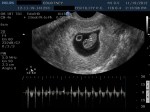

- 8w1d – Heartbeat of 164 bpm

- 8w1d – CRL of 1.95 cm